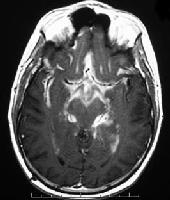

Patients present with signs and symptoms ranging from injury to nerves that traverse the subarachnoid space, direct tumor invasion of the brain or spinal cord, alteration in the local blood supply, obstruction of normal CSF flow pathways leading to increased intracranial pressure, or interference with normal brain function. Patients should have a physical examination with a careful neurologic evaluation; MRI of the brain and spine should also be done, if the patient has appropriate neurologic symptoms or signs. A definitive diagnosis is most commonly made by lumbar puncture. The CSF protein is typically increased, and there may be a pleocytosis or decreased glucose levels. The CSF cytology is positive approximately 50% of the time with the first lumbar puncture, and 85% of the time after three CSF examinations in patients who are ultimately proven to have neoplastic meningitis. However, the CSF cytology is persistently negative in 10% to 15% of patients with leptomeningeal carcinomatosis. In these cases, (1) a suspicious CSF examination (eg, increased protein, low glucose, and/or a pleocytosis) combined with suggestive clinical findings (eg, multifocal neuraxis involvement, such as cranial nerve palsies and a lumbar radiculopathy that cannot be explained otherwise); and/or (2) suggestive radiologic features (eg, subarachnoid masses, diffuse contrast enhancement of the meninges, or hydrocephalus without a mass lesion) can be sufficient to treat when the patient is known to have a systemic malignancy. Although a positive CSF cytology in patients with solid tumors is virtually always diagnostic, reactive lymphocytes from infections (eg, herpes zoster infection) can often be mistaken for malignant lymphocytes.